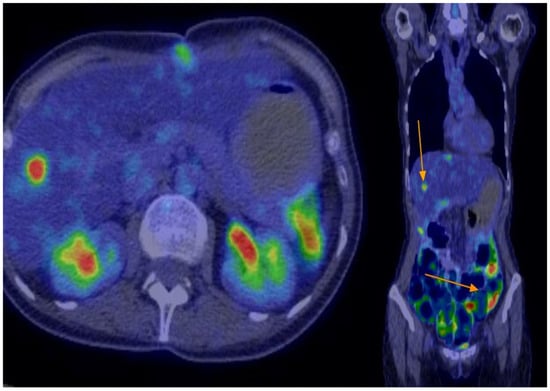

Treatment was initiated with nivolumab 480 mg every 4 weeks and cabozantinib 40 mg daily. This regimen was maintained for the first three months, with scheduled imaging assessments—including PET-CT and hepatic MRI—at 3 to 4 months to evaluate both structural changes and metabolic activity of liver and residual peritoneal metastases. Monthly clinical and laboratory follow-up was performed, during which the patient showed good treatment tolerance without adverse events. Follow-up imaging at 3 and 6 months demonstrated no disease progression on PET-CT or hepatic MRI. At the 9-month evaluation, liver MRI identified three new small lesions (measuring 5–8 mm). Two of these showed slight dimensional progression, while one showed regression compared to the previous scan. According to RECIST 1.1 criteria, the overall assessment remained consistent with stable disease. To further evaluate metabolic activity, an additional PET-CT was performed (see Figure 4). It revealed multiple nodular and flat lesions located along the anterior peritoneal surface of segments III, IV, VI, and VIII (SUV max up to 6.66; largest lesion 5.3 × 1.3 cm), as well as intraparenchymal lesions in segment V (SUV max 4.62) and segment VI (1.5 × 1.3 cm, SUV max 9.22). On PET-CT prior to treatment, the hepatic lesion had an SUVmax of 12.4, which decreased to 5.2 at 6 months and remained stable at 18 months. The maximum SUV of the largest peritoneal nodule decreased from 11.5 to 7.3 cm. These findings supported the clinical observation of durable disease control. Despite these findings, the disease remained classified as stable.

Figure 4. Treatment response on PET-CT evaluation at 9 months.